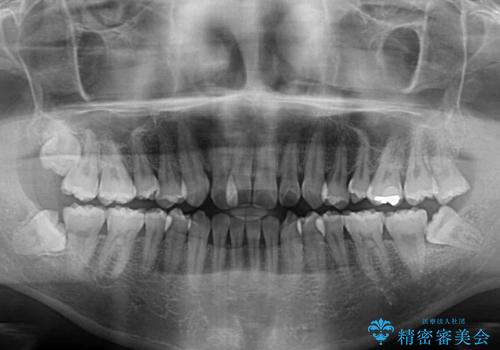

- 上下の前歯の反対咬合を気にして来院された患者様です。

インビザラインを用い、下顎はIPR(歯と歯の間を削る)と歯列全体を後方に移動させ、上顎は前歯を持ち上げることで、反対咬合を改善していくこととしました。

八重歯の歯根が見えている点も気になっているので、矯正歯科治療後に歯肉移植による根面被覆を行うこととしました。